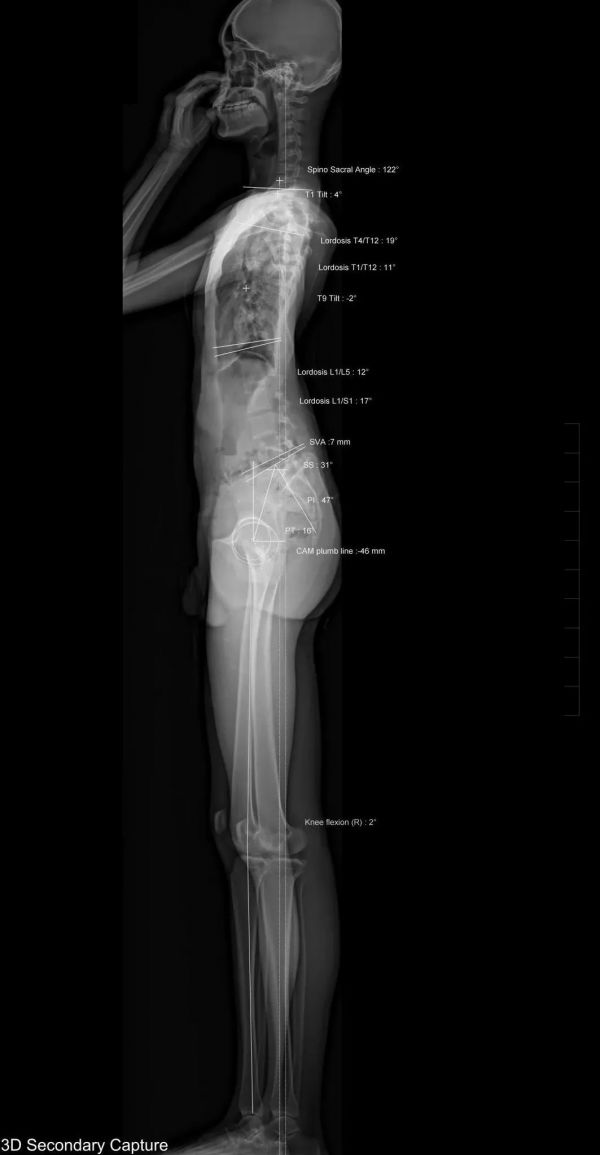

檢查項(xiàng)目:EOS全身正側(cè)位

影像所見(jiàn)

胸7、11、12蝴蝶椎體畸形,胸6-8椎間隙、胸10-11椎間隙顯著變窄。脊柱側(cè)彎,胸椎以胸9為中心向右側(cè)彎,Cobb角約20°;腰椎以腰3椎體為中心向左側(cè)彎,Cobb角約28°。胸腰段脊椎前凸。

測(cè)量參數(shù)如下:胸椎后凸角 (TK:T1/T12)約11°,腰椎前凸角 《LL:L1/S1) 約17°,矢狀面軸向距離 (SVA) 7mm,骨盆入射角 (FI)約47°。

雙側(cè)下肢長(zhǎng)度測(cè)量如下:右側(cè)股骨頭中心至脛骨 下穹隆長(zhǎng)度約829mm,左側(cè)長(zhǎng)度約820mm。左側(cè)膝關(guān)節(jié)中心向外偏離Mikulicz線10mm。

影像結(jié)果

胸7、11、12蝴蝶椎體畸形,胸6-8、胸10-11阻滯椎,脊椎側(cè)彎;左膝關(guān)節(jié)內(nèi)翻。